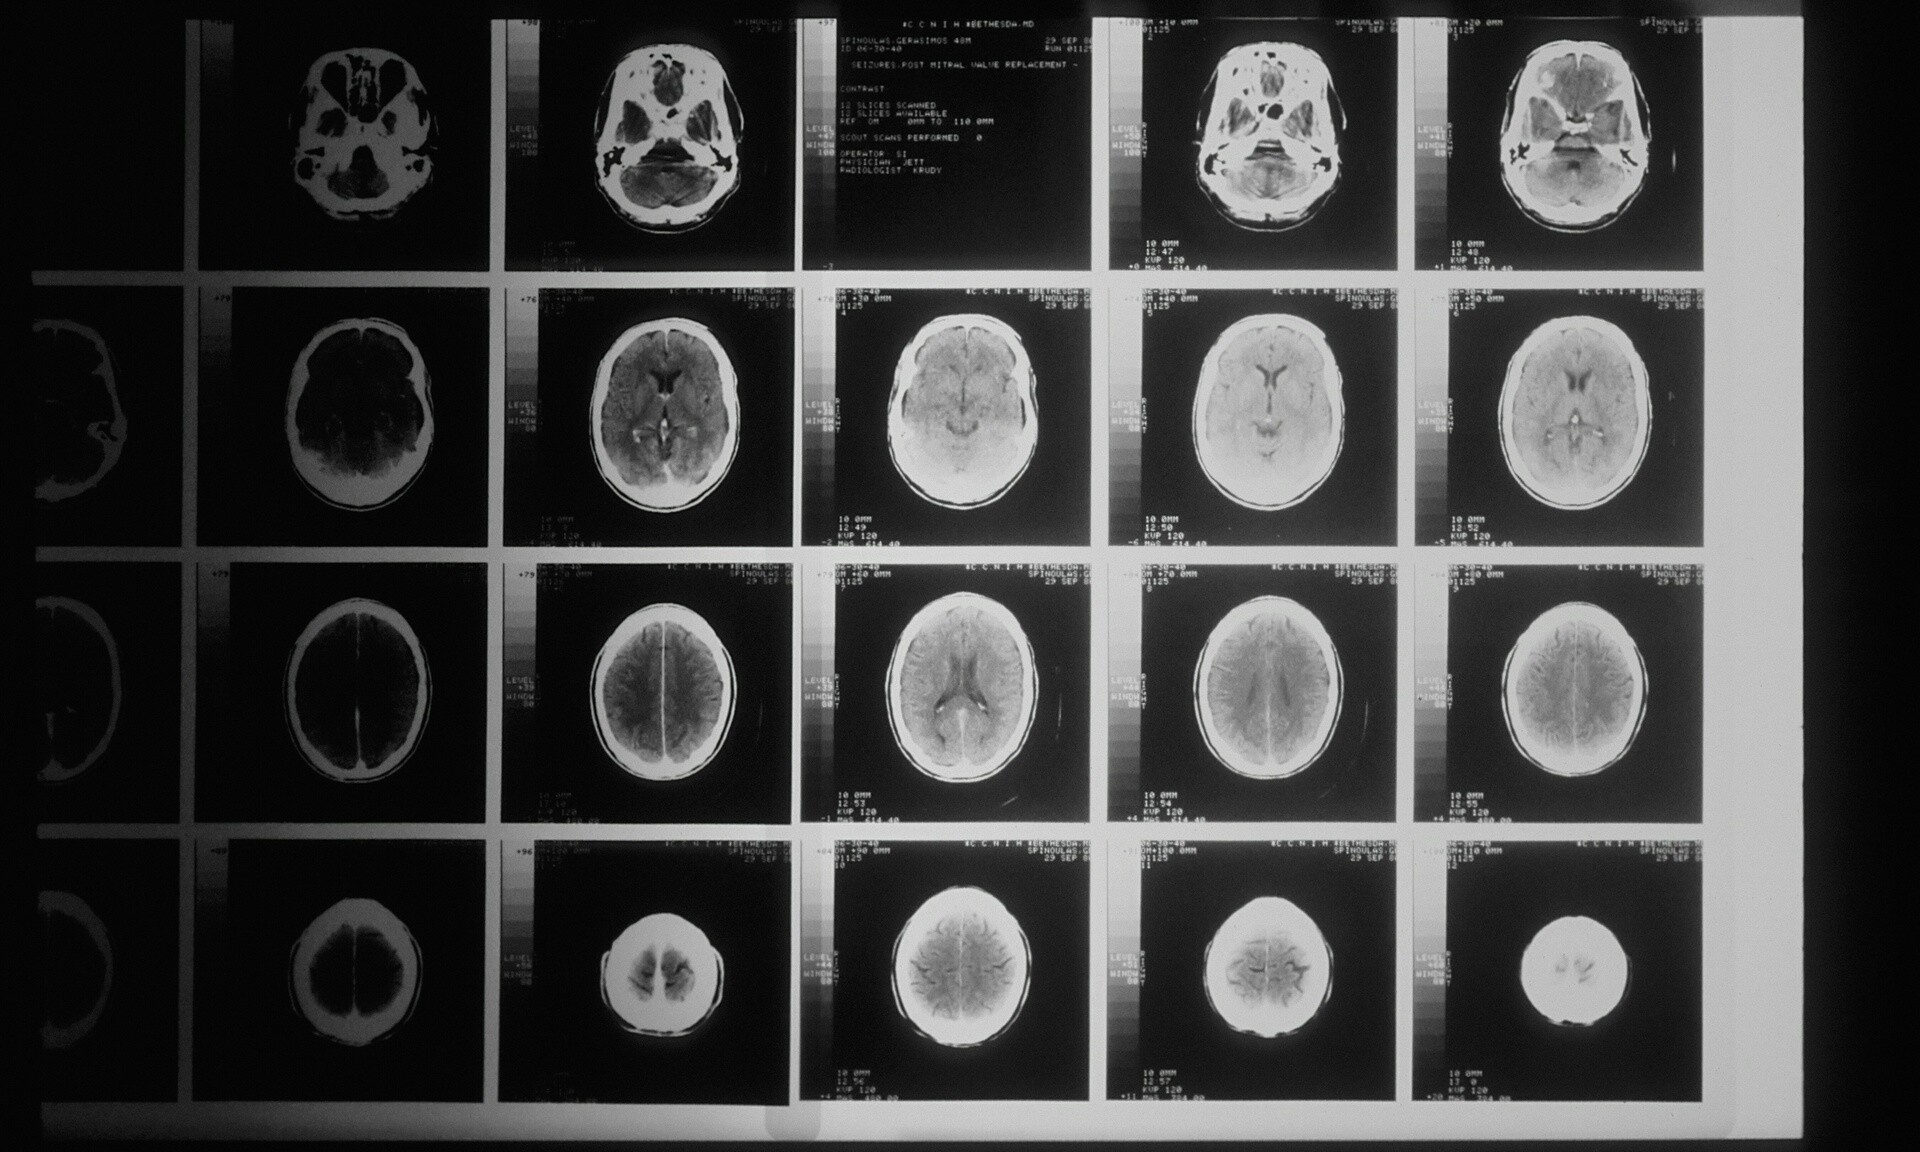

Συναγερμός στην ιατρική κοινότητα του Καναδά, για άγνωστη εγκεφαλική ασθένεια, που είχε προσβάλλει περισσότερους από 200 ανθρώπους.

Το 2021, οι υγειονομικές αρχές του New Brunswick προειδοποίησαν ότι περισσότεροι από 40 κάτοικοι έπασχαν από ένα πιθανό άγνωστο νευρολογικό σύνδρομο, με συμπτώματα παρόμοια με εκείνα της εκφυλιστικής εγκεφαλικής διαταραχής, που ονομάζεται Creutzfeldt–Jakob.

Τα συμπτώματα ήταν ποικίλα και κατά περιπτώσεις έντονα. Σε ορισμένους ασθενείς άρχισαν να τρέχουν σάλια και άλλοι ένιωθαν σαν να σέρνονται έντομα στο δέρμα τους. Ωστόσο, έναν χρόνο αργότερα, μία ανεξάρτητη επιτροπή εποπτείας που δημιουργήθηκε από την επαρχία διαπίστωσε ότι στην ομάδα των ασθενών πιθανότατα είχε δοθεί λανθασμένη διάγνωση.